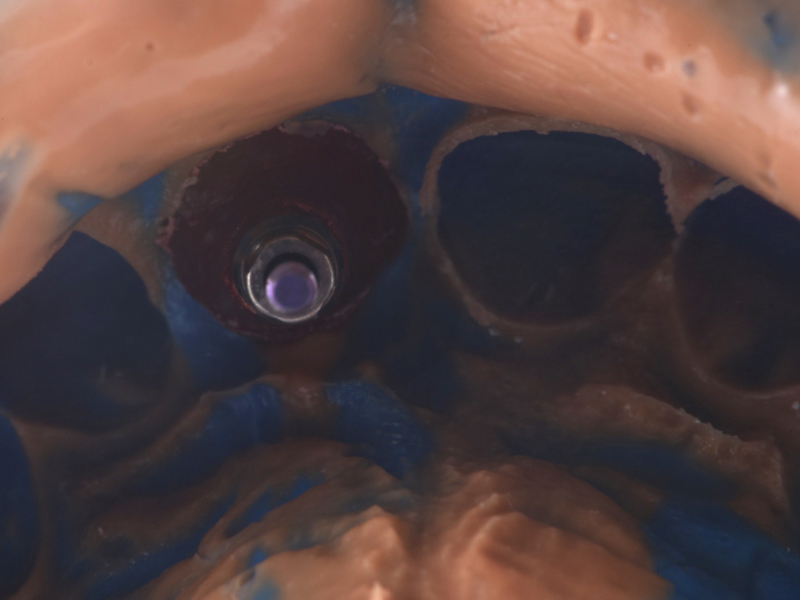

Once the optimal emergence profile has been developed, we need to communicate and transfer this information properly to the laboratory. Unfortunately, all implant companies provide stock round impression copings that do not precisely transfer the soft-tissue contours. A simple protocol to communicate this information is described here.

This visual essay walks through a step-by-step description of how to fabricate a personalized impression coping with transfer ofthe peri-implant tissue anatomy properly.